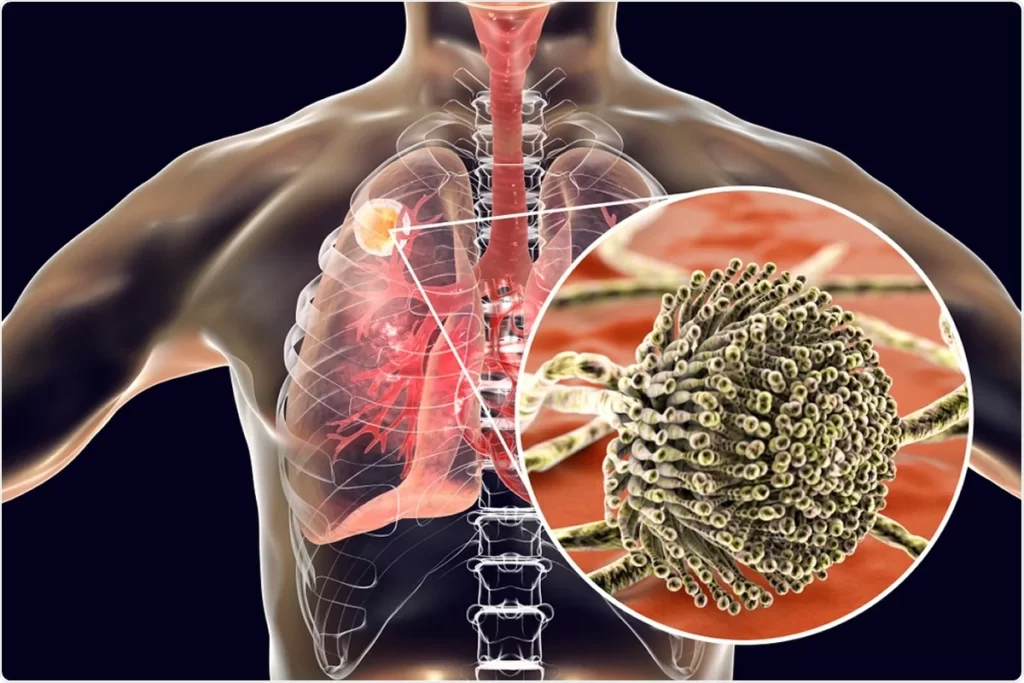

داء الرشاشيات العلاج و التشخيص في تركيا

كما يعرف داء الرشاشيات هو حالة يسببها العفن الرشاشيات. كما هناك عدة أنواع مختلفة من داء الرشاشيات يؤثر معظمها على الرئتين ويسبب صعوبات في التنفس.

أشكال داء الرشاشيات

قد تحدث الإصابة بداءُ الرَّشَّاشِيَّات بأشكال عدة: